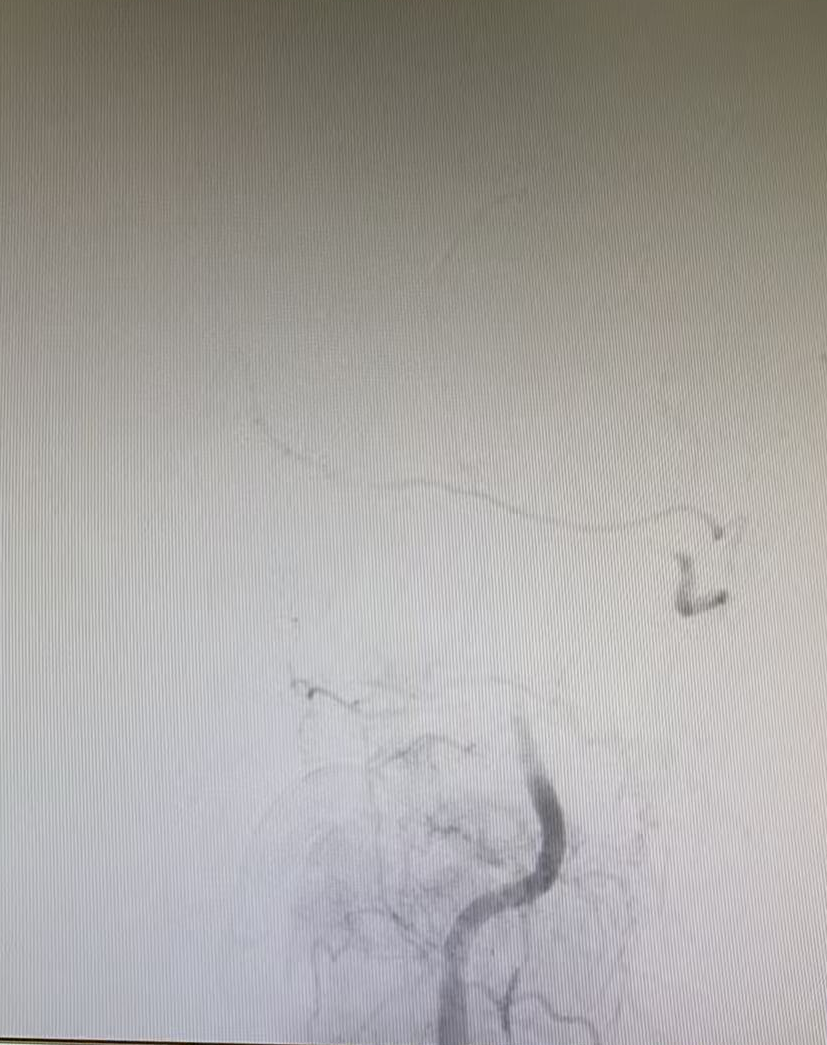

與家屬充分溝通并取得同意后,晚上7點42分,患者被推入介入手術(shù)室。手術(shù)團(tuán)隊經(jīng)驗豐富,操作精準(zhǔn),晚上7點50分成功建立手術(shù)通路,在DSA影像引導(dǎo)下,微導(dǎo)絲與微導(dǎo)管精準(zhǔn)穿越閉塞血管段。晚上8點07分,堵塞的椎基底動脈被成功開通,從進(jìn)入介入室到血管再通,僅用時25分鐘。

但挑戰(zhàn)還在繼續(xù),血管開通后發(fā)現(xiàn)內(nèi)部存在嚴(yán)重狹窄,遠(yuǎn)端血流灌注不足,團(tuán)隊隨即進(jìn)行球囊擴(kuò)張改善血流,但血管回縮明顯。為確保持久通暢,團(tuán)隊果斷植入一枚支架。最終,血管形態(tài)恢復(fù)良好,血流達(dá)到最佳標(biāo)準(zhǔn),缺血的大腦獲得了充足的血液供應(yīng)。

術(shù)前血管閉塞

球囊擴(kuò)張術(shù)后

支架置入后